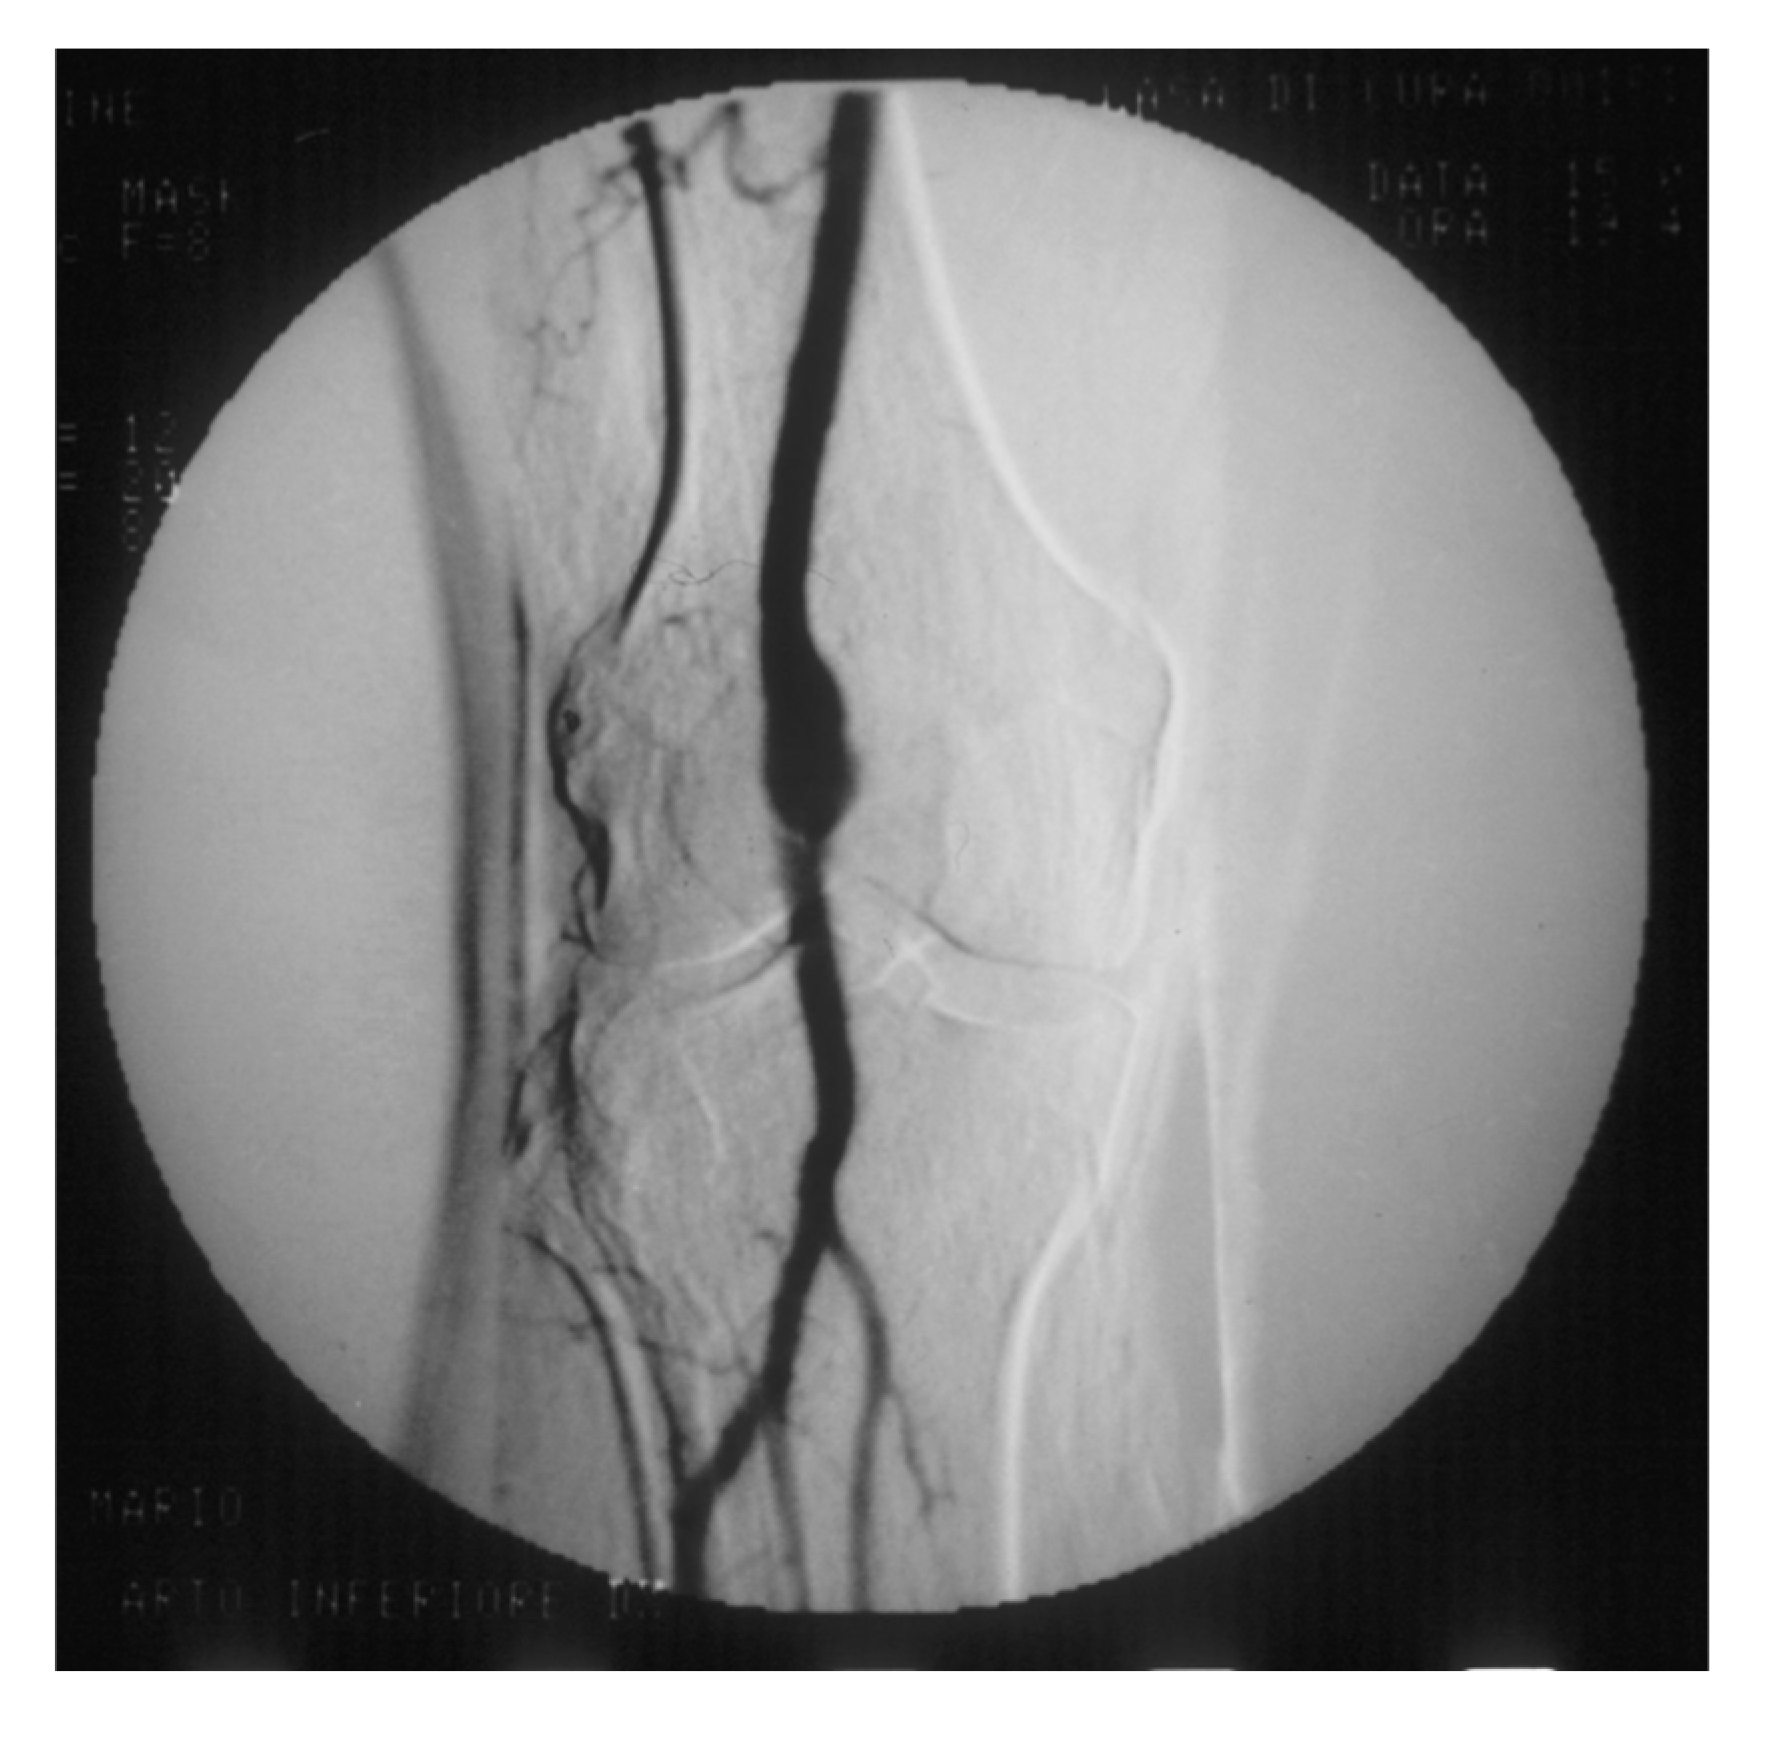

Figure 8. Arteriography showing popliteal artery aneurysm. The physiologic flexion movement of the knee can dislocate part of the mural thrombus, which embolizes and occludes some tibial arteries, giving rise to clinical pictures ranging from an asymptomatic state to intermittent claudication, or chronic limb-threatening ischemia, or acute limb ischemia.

PAAs should be detected, not much for the risk of rupture, which is rare, but for their risk of embolization and thrombosis. The physiologic flexion of the knee can act as a tremendous stress for the parietal thrombus of the PAA, potentially causing paroxysmal, multiple, and insidious episodes of asymptomatic microembolization to the tibial arteries (Figure 8).

As a consequence, these latter can progressively obstruct, drastically reducing the run-off of the popliteal artery and giving rise to clinical picture ranging from blue toe syndrome, or LEAD with IC up to chronic limb-threatening ischemia. These patients may be clinically indistinguishable from those presenting with LEAD. Therefore a careful examination is required to distinguish chronically symptomatic PAA patients from those with symptoms due to LEAD.

PAA can also thrombose entirely due to the affected tibial out-flow, so it manifests itself with acute lower limb ischemia: limb loss can reach 14% in these patients [60,63].